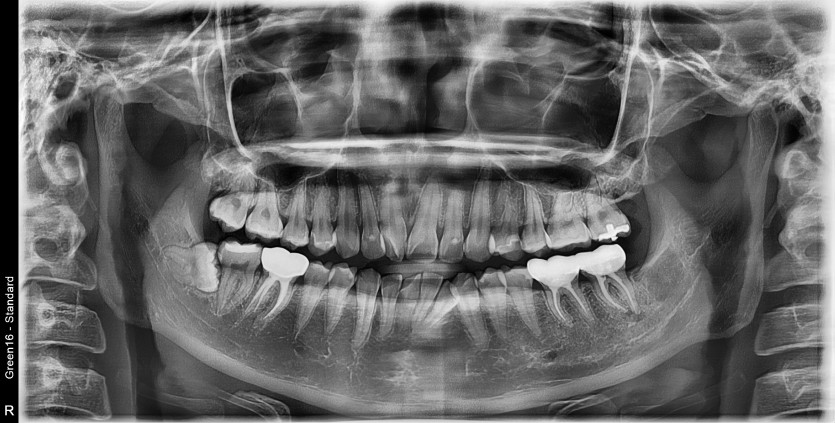

#48 사랑니 발치

구강 외과 전문의가 당일 발치했습니다.